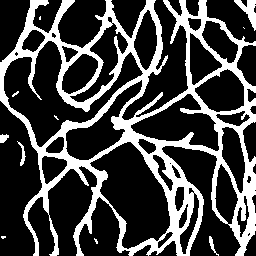

Semantic segmentation of blood vessels is an important task in medical image analysis, but its progress is often hindered by the scarcity of large annotated datasets and the poor generalization of models across different imaging modalities. A key aspect is the tendency of Convolutional Neural Networks (CNNs) to learn texture-based features, which limits their performance when applied to new domains with different visual characteristics. We hypothesize that leveraging geometric priors of vessel shapes, such as their tubular and branching nature, can lead to more robust and data-efficient models. To investigate this, we introduce VessShape, a methodology for generating large-scale 2D synthetic datasets designed to instill a shape bias in segmentation models. VessShape images contain procedurally generated tubular geometries combined with a wide variety of foreground and background textures, encouraging models to learn shape cues rather than textures. We demonstrate that a model pre-trained on VessShape images achieves strong few-shot segmentation performance on two real-world datasets from different domains, requiring only four to ten samples for fine-tuning. Furthermore, the model exhibits notable zero-shot capabilities, effectively segmenting vessels in unseen domains without any target-specific training. Our results indicate that pre-training with a strong shape bias can be an effective strategy to overcome data scarcity and improve model generalization in blood vessel segmentation.